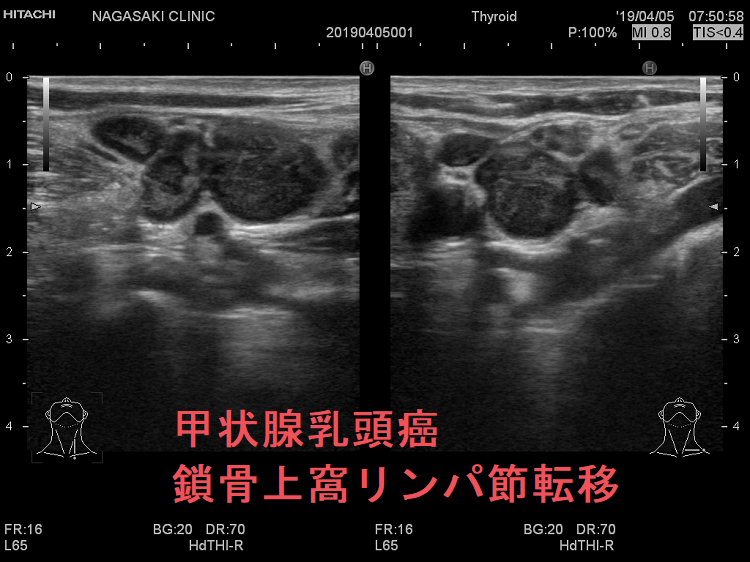

甲状腺乳頭癌の鎖骨上窩リンパ節転移再発

甲状腺乳頭癌鎖骨上窩リンパ節転移再発

ケース①

甲状腺乳頭癌の鎖骨上窩リンパ節転移再発 超音波(エコー)画像

鎖骨上窩は予防的リンパ節郭清(前頚部リンパ節郭清)の範囲外につき、術後リンパ節再発のピットフォールとなります(意外とよく見つかります)。

甲状腺乳頭癌が左鎖骨上窩リンパ節に転移して再発すると、左静脈角から血流に乗って全身へ運ばれ、遠隔転移を来します。左鎖骨上窩の転移リンパ節をウィルヒョウリンパ節、左鎖骨上窩リンパ節転移をウィルヒョウ転移と言います。

甲状腺乳頭癌 鎖骨上窩リンパ節転移 超音波(エコー)画像

甲状腺乳頭癌 左鎖骨上窩リンパ節転移 超音波(エコー)画像;いびつな形で、周囲との境界が一部不明瞭化して浸潤が疑われる。リンパ門は消失し、砂粒状石灰化が著明

甲状腺乳頭癌 鎖骨上窩リンパ節転移 超音波(エコー)画像 ドプラーモード

甲状腺乳頭癌 左鎖骨上窩リンパ節転移 超音波(エコー)画像 ドプラーモード;内部に異常な走行の血管を認め、血流豊富。